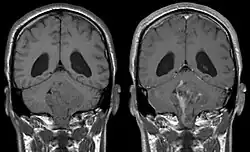

Ependymoma of 4.ventricle in MRI. -

Ependymoma of 4.ventricle in MRI. Left without, right with contrast-enhancement.